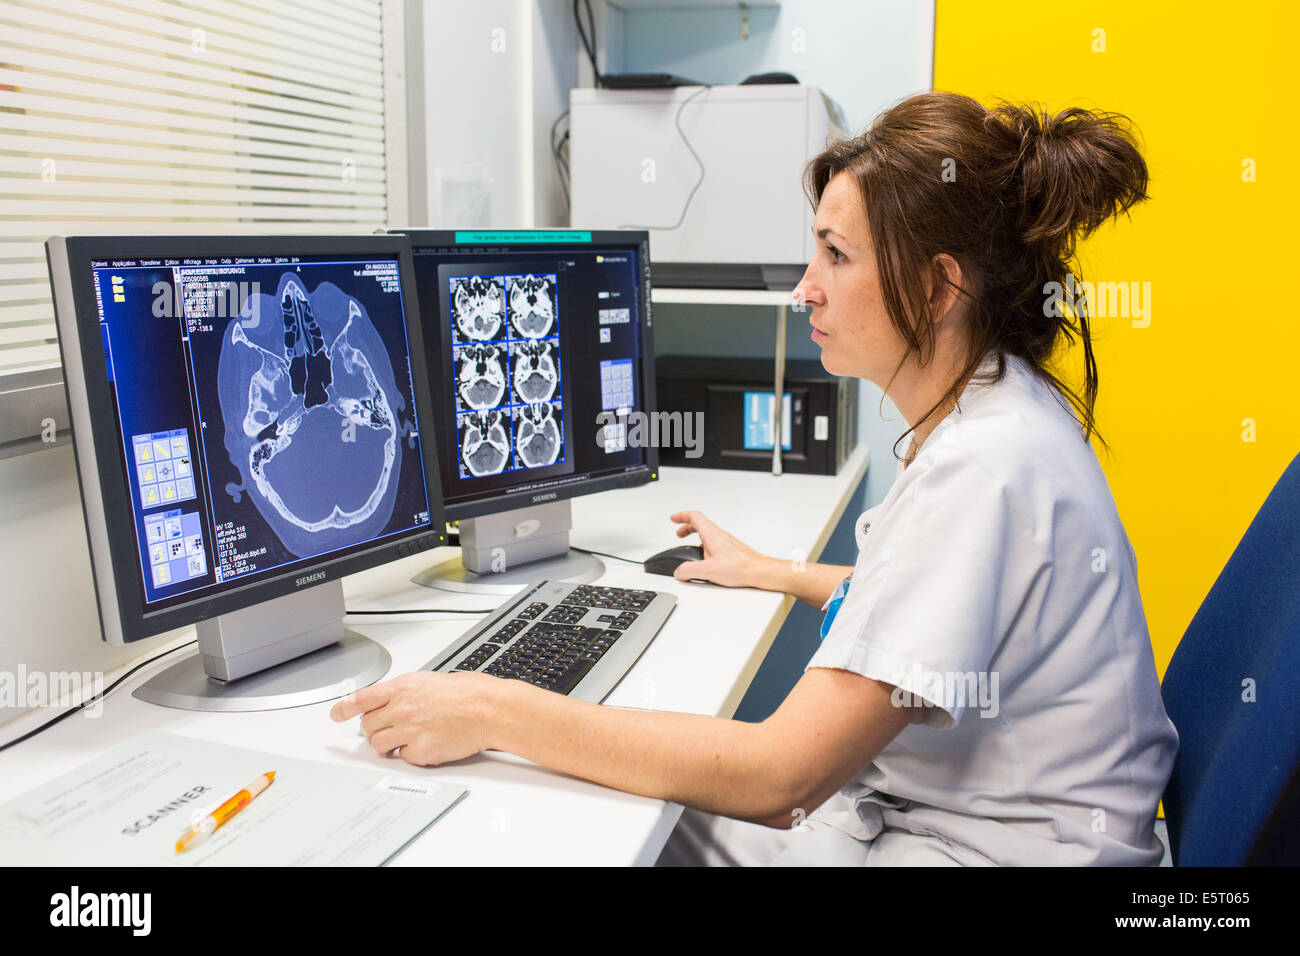

La TDM cérébrale, l'hôpital d'Angoulême, France . Banque D'Imageshttps://www.alamyimages.fr/image-license-details/?v=1https://www.alamyimages.fr/photo-image-la-tdm-cerebrale-l-hopital-d-angouleme-france-72441773.html

La TDM cérébrale, l'hôpital d'Angoulême, France . Banque D'Imageshttps://www.alamyimages.fr/image-license-details/?v=1https://www.alamyimages.fr/photo-image-la-tdm-cerebrale-l-hopital-d-angouleme-france-72441773.htmlRME5T065–La TDM cérébrale, l'hôpital d'Angoulême, France .